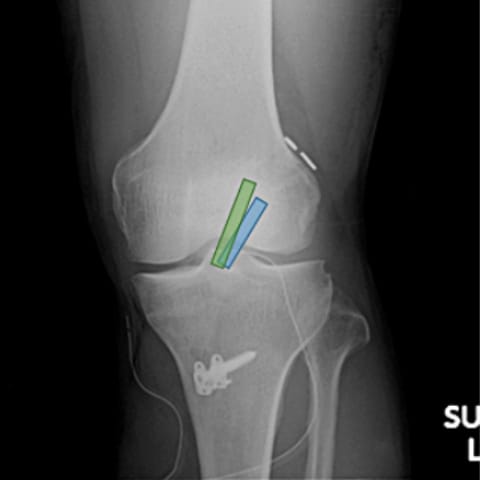

手術は自身のハムストリングスという腱や膝蓋腱や大腿四頭筋腱という膝の前の膝蓋骨(いわゆるお皿の骨)とその上下の腱の一部を用いて、靱帯を再建します。できる限り解剖学的に正常の前十字靱帯に近いように再建する方法を行っています。入院期間は2週間程度で退院となります。術後は筋力の回復をみながらリハビリを行い、術後約3カ月でジョギングや水泳よりスポーツ復帰を開始します。競技や再建方法にもよりますが、最終的な試合への復帰は10か月前後かかることが多いです。

正常解剖に近づけるため、太ももの骨とすねの骨に2個ずつトンネルをあけ、2本の移植腱(青色・緑色)で再建します

術後単純X線